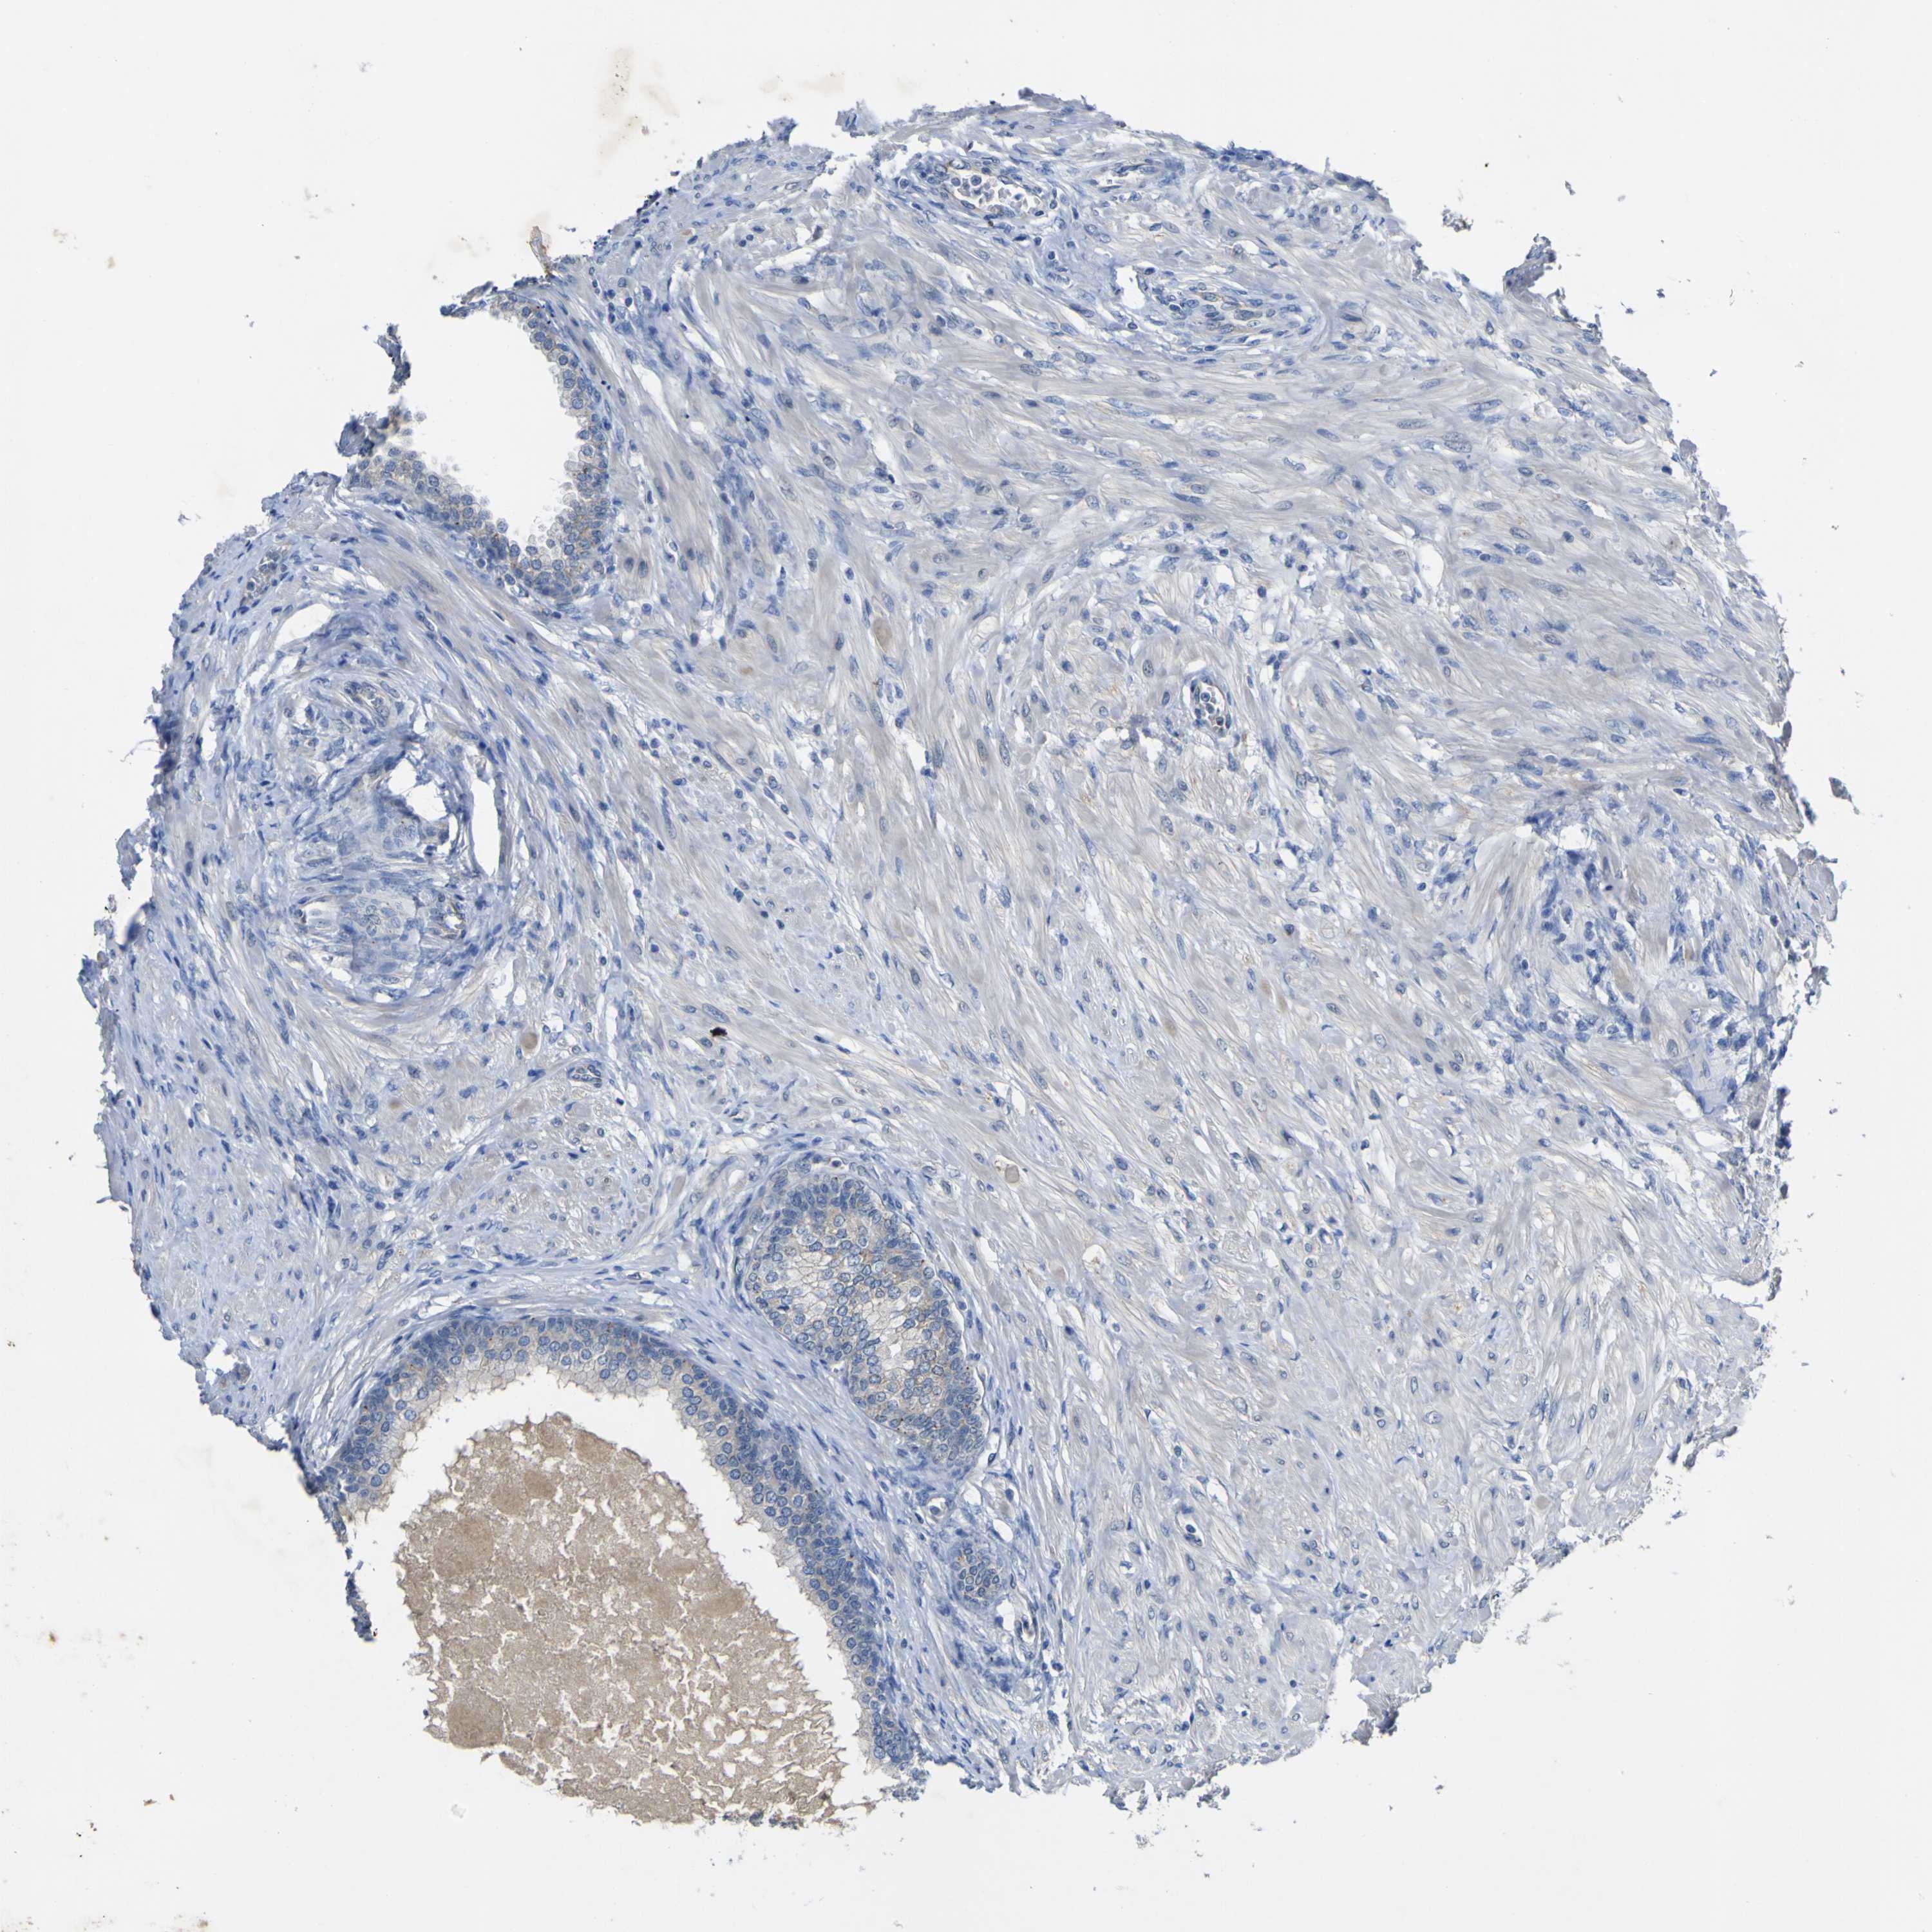

Tissue expression of LDLR Staining in prostate The Human Protein Atlas Protein Atlas Ldlr  Cytoplasmic expression in a subset of cells including cells in the gastrointestinal tract, leydig. Correlation analysis based on mrna. Summary of ldlr expression in human tissue. The pathology section contains mrna and protein expression data from 17 different forms of human cancer. The structure section provides predicted structures from the alphafold protein structure database and includes. Low density lipoprotein receptor. Protein Atlas Ldlr.

From www.proteinatlas.org